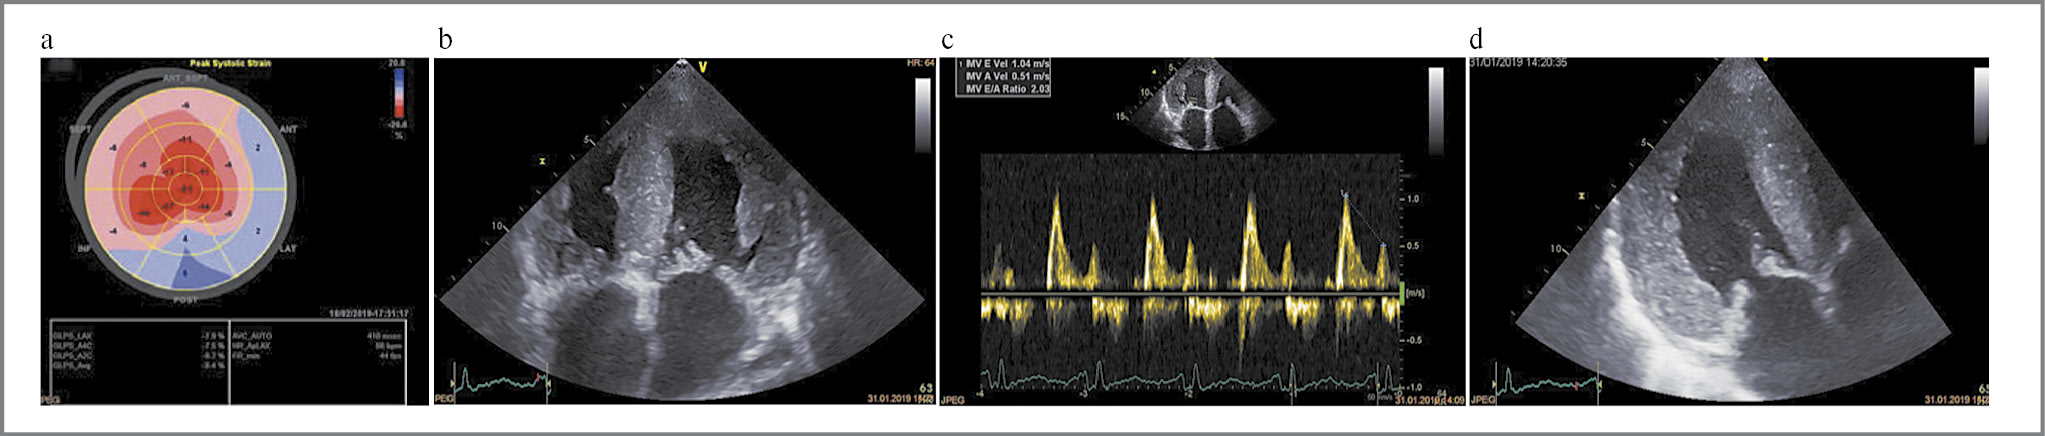

Рис. 4. Клинический пример 1. Пациент А. с AL-амилоидозом фенотипа ГФ+РФ: a, b – бивентрикулярное утолщение стенок со специфической «светящейся» структурой, дилатация полостей предсердий; c – рестриктивное нарушение диастолической функции ЛЖ (E/A>2); d – характерный паттерн нарушения глобальной продольной деформации ЛЖ в виде базально-апикального градиента.

Fig. 4. Clinical case 1. Patient A. with AL-amyloidosis of the HP+RP phenotype: a, b – biventricular thickening of the walls with a specific "luminous" structure and atrial cavity dilation; c – restrictive impairment of LV diastolic function (E/A>2); d – a typical pattern of impaired LV global longitudinal strain with a basal-apical gradient.

Главным образом встречалось сочетание ГФ+РФ (43%) (рис. 4) и ГФ (30%) (рис. 5). У 1 (1,8%) пациентки присутствовал истинно РФ, характеризующийся дилатацией полостей предсердий, выраженным нарушением диастолической функции миокарда ЛЖ по рестриктивному типу при отсутствии утолщения стенок ЛЖ более чем 1,2 см (рис. 6).